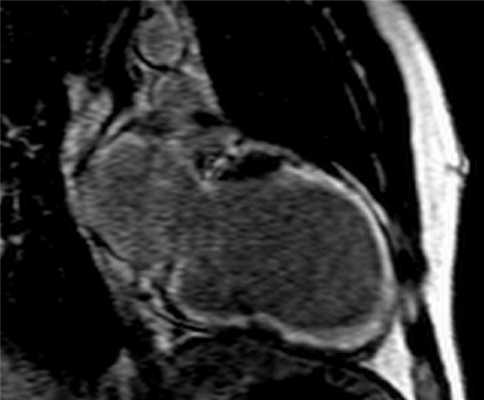

- диагностика миокардита. Миокардит визуализируется с помощью МРТ с контрастным усилением, как зоны гиперусиления с интрамуральной и субэпикардиальной локализацией. Так же можно определить воспалительный отек тканей сердца.

Рисунок 4. МРТ. Четырехкамерное сечение сердца. Миокардит, субэпикардиальное и интрамиокардиальное накопление контрастного препарата.